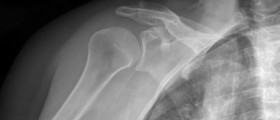

Joint of the shoulder has several parts and one with the biggest significance is the rotator cuff. The rotator cuff muscles are made of several muscle and tendon groups, which are responsible for keeping the shoulder in its normal position. They are responsible for enabling us to reach and grab something over our heads or for lifting heavy objects. These muscles and tendons are responsible for these movements since they give the power and stability to the shoulder. Athletes and adults in general have great problems with injuries of the rotator cuff and some numbers say that more than 4.1 million Americans looked for help in 2006 for the rotator cuff injury.

Muscle weakness, tenderness and constant pain, along with the night pain, are some of the most common symptoms of the rotator cuff injury. Pain can be experienced while lying on the hurt shoulder, and it is important to see a doctor if the pain remains and does not go away. Athletes may even need to end their careers because of the rotator cuff injury if there is a complete tear of a tendon, or even several tears. The full functionally of the shoulder may not be regained after the treatment of such an injury. In these cases, the complete functionality of the joint can be achieved with the use of a surgery.

Seniors and mature adults find this kind of injury very common since the tendons in the rotator cuff become tear prone as we enter the final stage of life. If the athletic exertion is repetitive, which is usually the case with athletes, there is a chance they will suffer from a rotator cuff injury. This is most common among those who play sports that involve the use of a shoulder for a longer period of time, such as golf, tennis or bowling. Stress placed on the tendons of the rotator cuff during these sports is truly great. The chances of injuring the rotator cuff increase due to a career in the construction business, poor posture and age.Acute and Chronic Tear

When we fall, we usually stretch our arm to make the fall less painful, and this is one of the situations that can lead to the rotator cuff injury. Actions like this, which are powerful and sudden, can lead to the acute tear. But the most important factor for the development of chronic tear is time. Age is an important factor in the development of the chronic tear as well. The most common location for this type of injury is at or around the tendon of the bone interface.